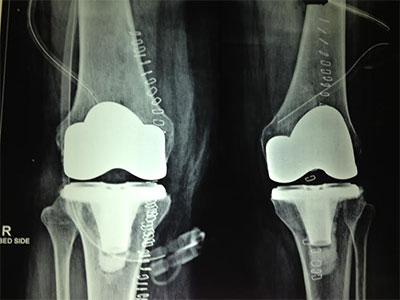

Total Knee Replacement is a procedure in which the parts of the bones that rub together are resurfaced with metal and plastic implants. Precision instruments are used to remove and replace damaged parts of the bone with implants. The surface of the femur is replaced with a rounded metal component that matches closely the curve of your natural bone. And the surface of the tibia/leg bone is substituted with a smooth plastic component.

Prior to surgery an IV line will be inserted into your arm to administer medication during the operation. Thereafter anesthesia is administered in the OT. Once anesthesia has taken effect, the knee is scrubbed and sterilized. The surgery then begins with an incision to expose the knee joint. The surgeon then uses precision guides and instruments to remove damaged surfaces. The ends of the bones are then shaped to accept the implants. The implants are then fixed, and the incision closed. A sterile bandage is applied to the wound and routine post operative care will follow as anesthesia wears off.

Bone cement is used to secure the knee implants.